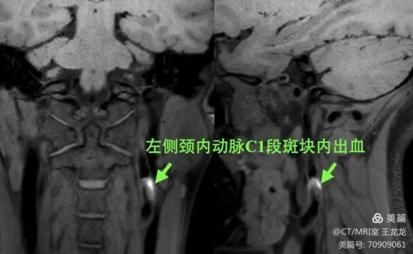

颈内动脉斑块内出血